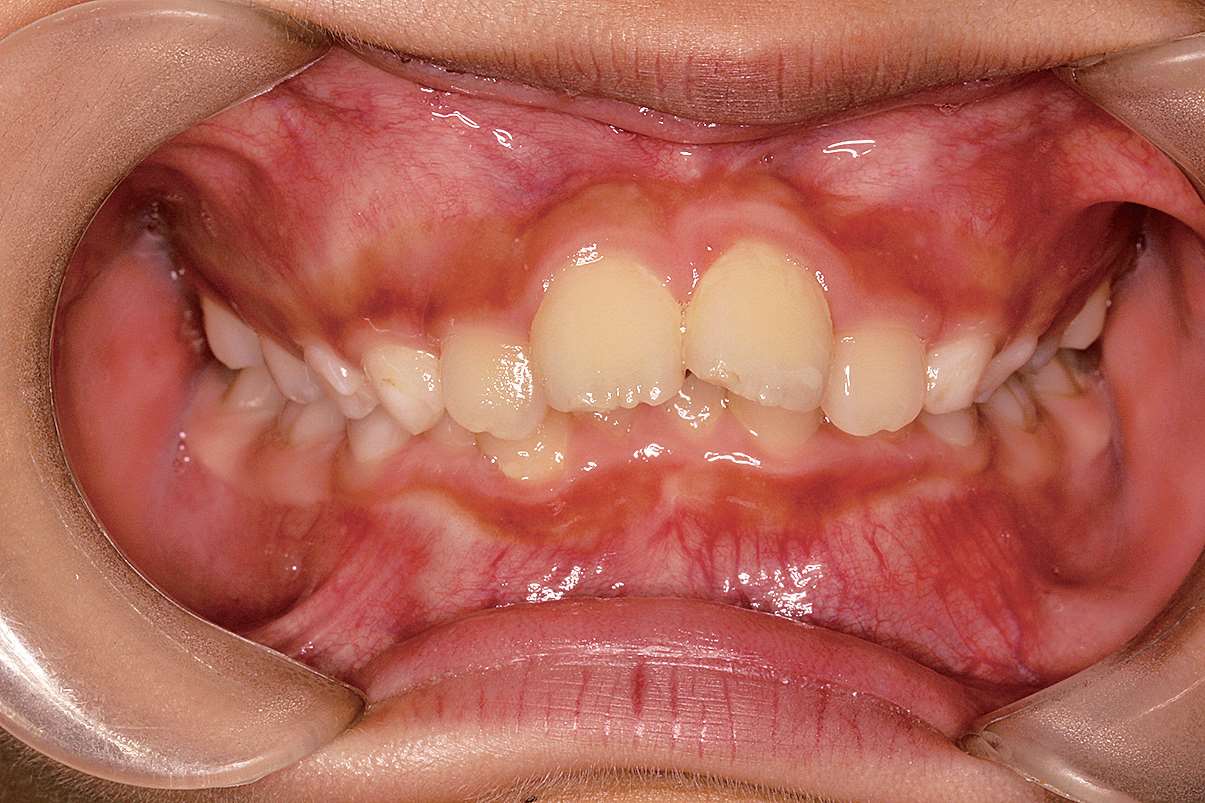

图 2-5 Ⅱ类 1 分类口内照片